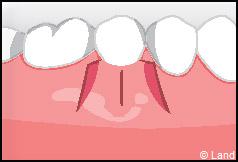

Les greffes de conjonctifs enfouis :

Destinées aux zones esthétiques, elles consistent à prélever la partie profonde du palais (site donneur).

Ce greffon est ensuite inséré sous la gencive au niveau de la récession (site receveur).